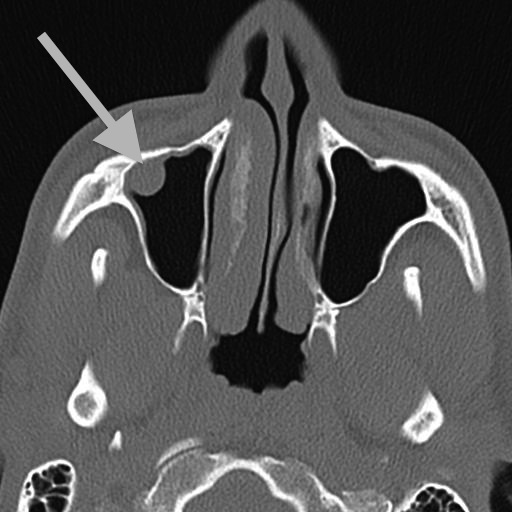

While my right inferior turbinate is the major target here, other slices show the middle turbinates:

I presume that both “turbinate” and the alternate name “nasal concha” refer to the coiled shape here, like a turbine or a conch shell.

Working together the turbinates channel airflow through three primary paths in each nasal passage: below the inferior turbinate, between the inferior and the middle turbinates, and above the middle turbinate.

The Sinus Polyp

Before the CT scan was conducted, we expected to see a deviated septum and funky turbinates. But an unknown was also revealed: unwelcome matter in my right maxillary sinus, the cavity behind my cheek bone. I still don’t know what this gunk was, but most likely a polyp or overgrowth of the mucous membrane.

Once this was revealed by the CT scans, my doctor added “antrostomy” to the list of interventions included in the surgery. While slicing and dicing in my nasal passages, he took a detour into my right maxillary sinus to dig out the gunk.